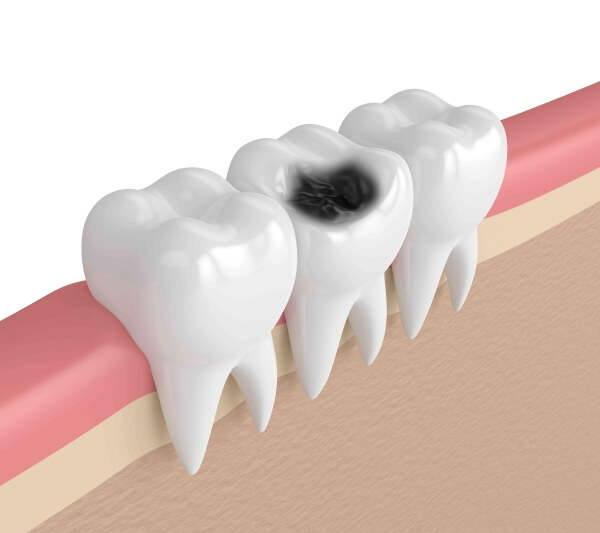

- Sâu thân răng: phần thân răng bị sâu răng tàn phá nghiêm trọng và không thể sử dụng phương pháp trám thẩm mỹ để điều trị dẫn tới viêm tủy, đau nhức kéo dài. Lúc này, giải pháp duy nhất là loại bỏ phần tủy hỏng để ngăn ngừa tình trạng viêm nhiễm trở nên xấu hơn sau đó tiến hành bọc răng sứ để phục hồi chức năng của răng và tránh gây vỡ, hỏng về sau.

Hình ảnh sâu thân răng